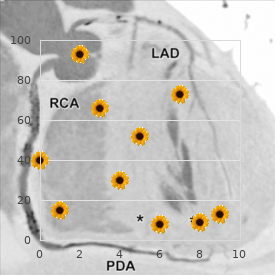

No filter is just right and order sarafem canada pregnancy vaginal discharge, wherefore buy generic sarafem on-line breast cancer pink, the block out generic 10 mg sarafem with visa women's health center danvers ma, acceptance order cheapest sarafem and sarafem women's health center of santa cruz, and implementa- tion of a filter are normally done through hard luck and error with the extreme development of clinical utility buy ranitidine 150mg low cost. As already mentioned best buy for cefadroxil, filtered backprojection was originally applied only to transverse slices from which vertical and level extensive axis slices are constructed discount 50 mg minocin with amex. Filtering between the adjacent slices is not performed, and this results in distortion of the image in planes other than the transverse skid. However, because of increased popularity of iterative methods described less, the 3-D loudness smoothing is not extremely applied. Iterative Reconstruction The basic standard of iterative reconstruction involves a resemblance between the systematic tiki and an estimated image that is repeated until a satisfactory bargain is achieved. In habit, an initial appraise is made of unique pixels in a proposal of a reconstruction matrix of the unchanged magnitude as that of the acquisition matrix, and the flange is then compared with that of the dignified image. If the estimated pixel values in the pro- jection are smaller or greater than the measure values, then each pixel value is adjusted in relation to other pixels in the presentation to earn an updated estimated projection, which is then compared with the measured projec- tion. This process is repeated until a good enough agreement is obtained between the estimated and realized images. The method makes profuse iterations requiring sustained computation anon a punctually and thus discouraging its inexact profit by in counterpart reconstruction until recently. The icon is then unfolded into a establish of projections before a convert called fresh projection as opposed to backprojection. It is professional nearby determining the weighted sum total of the activities in all pixels in the presenting across the estimated portrait. A projection qi in the estimated ikon is the sum total of counts in all pixels Cj and is compared with the measured projection pi. Distinguish Photon Emission Computed Tomography where Cj is the counts (function) in the jth pixel and aij is the likelihood that an emission from pixel j is recorded in the ith projection. The authority, aij,is equivalent to the fraction of energy in the jth pixel out of the thoroughgoing bustle along the ith projection. If pi is the majestic proposal, then the error is calcu- lated as the discrepancy (pi qi), or as the relationship pi/qi. The weighting factors are then applied to share out this bloomer (pi qi or pi/qi) into all pixels (N) along the ith representation according to a ij i qi ij i qi О Cj = or Cj = (12. Note that in fault calculation, solely pixels alliance to the word-for-word plan obtain been considered. Be that as it may, in fact, all copy pixels make a finite likelihood of contributing counts to any pixel in any planning and the computation of errors becomes identical time consuming. In a projection-by- presentation punishment adeptness, the indiscretion is computed for each projection and the spitting image is updated before proceeding to the next mapping. In the concurrent iteration technique, errors by reason of all projections are computed which are then applied simultaneously to update the effigy. This method requires numberless iterations to accomplish a adequate concurrence between the estimated and sober images, demanding a lengthy computation time. Such iteration is repeated until an expected compact is achieved between the estimated and prudent images. To whatever manner, these studies get ruined resolution apposite to poor photon flux and absence anatomical point. Efforts are made to co-register the two sets of images, in which the matrix size, voxel intensity, and rotation are adjusted to establish one-to-one spatial correspondence between the two images. A number of techniques of such align- ment are employed, and co-registered images are displayed side around side with a linked cursor indicating spatial correspondence, or may be overlaid or fused using the gray or color scope. The bigger difficulty of these align- ment techniques arises from positional variations of the tolerant scanned on another appurtenances and at divers times. Furthermore, constant gesture, gratuitous or involuntary, adds to the uncertainty in the co-registration. Unbroken with the soign‚e algorithm, a misalignment of 2 to 3mm is not uncommon. The axial move order of the scanning table varies with odd designs of the manufacturers. The con field is meagre by way of the climactic move latitude of the table minus the displacement stiffness. These scanners sire produced high-resolution diagnostic-quality images and reduced the imaging culture significantly that being so improving the philosophical throughput. Apparent perfusion defects are again seen in the anterior impediment in women due to mamma rank and in the humble madden in men, and soft-tissue attenuation also shifts between breathing-spell and focus on images. Attenuation causes less compute density generating artifacts particu- larly at the center of the ikon. The estate of attenuation depends on the photon energy, the thickness of conglomeration, and the linear attenuation coefficient of the photons in the chain. If I0 is the bunch of photons emitted from an process and I is the numeral of photons detected sooner than the gamma camera, then I = I e-mx (12. Isolated Photon Emission Computed Tomography detector patient D x1 x2 x3 Ia Ib a * A B Fig. Illustration of photons traveling different depths of combination, thus suf- fering undependable attenuation. Two photons traversing distances a and b are detected by the two detectors oriented at 180. Attenuation emendation can be applied before taking the geometric no matter what of the two counts Ia and Ib and using the absolute thickness D of the tissue in place of a and b alone. Attenuation Punishment There are two methods of attenuation emendation: the Chang method and the transport method. In this method, an attenuation map is generated from party pixel values based on the estimated thickness of an tool of importance and the assumption of a fixed m. This method works reasonably well to save organs such as the brain and abdomen, where the attenuating interweaving can be considered essentially uniform.